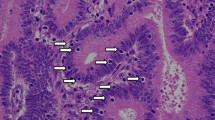

We first evaluated the expression of MMR proteins (MLH1, PMS2, MSH2, and MSH6) in 29 PD-CRC cases. Among the cases, 17 were MMR protein-proficient (MMR-P) and 12 were MMR protein-deficient (MMR-D) adenocarcinoma. In detail, 11 MMR-D cases showed dual loss of MLH1 and PMS2 and one MMR-D case showed dual loss of MSH2 and MSH6. Representative images and staining of MMR-D and MMR-P cases are shown in Fig. 1. Table 1 summarizes the correlations between clinicopathological factors and MMR protein expression. MMR-D cases were significantly correlated with age, tumor site, lymph node metastasis, pathological stage, and CD8+ TILs (Fig. 2a, b, d, e).

Representative images and staining of MMR-P and MMR-D cases. Representative features in MMR-D (a) and MMR-P (f). Immunohistochemistry of four MMR proteins. Loss of MLH1/PMS2 (b and c) and expression of MSH2/MSH6 (d and e) are shown in MMR-D. All four MMR proteins (g, h, i, and j) are detected in MMR-P. (a and f, HE; b and g, MLH1 immunostaining; c and h, PMS2 immunostaining; d and i, MSH2 immunostaining; e and j, MSH6 immunostaining)